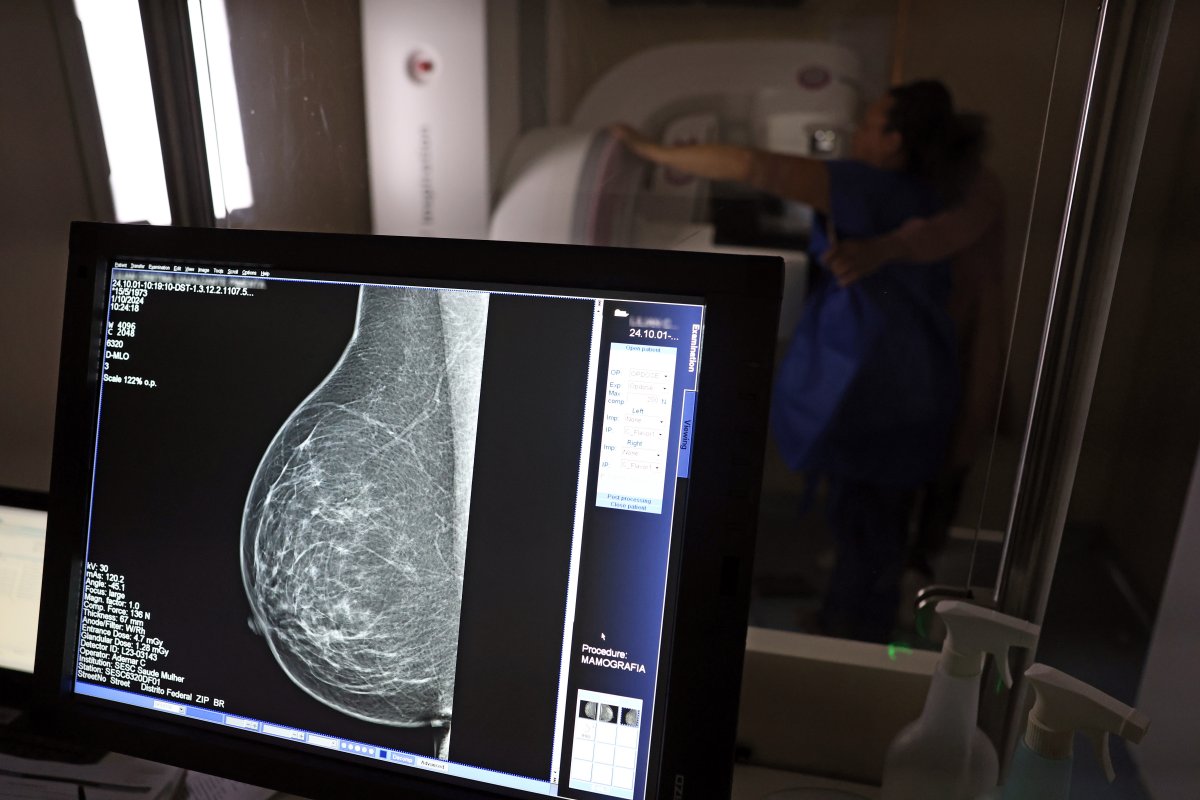

Foto: José Cruz/Agência Brasil

A pesquisa do Sistema de Vigilância de Fatores de Risco e Proteção para Doenças Crônicas por Inquérito Telefônico (Vigitel) do Ministério da Saúde divulgado em 28 de janeiro mostrou que a frequência de mulheres entre 50 e 69 anos de idade que fizeram exame de mamografia em algum momento de suas vidas aumentou no período entre 2007 e 2024, variando de 82,8% para 91,9%.